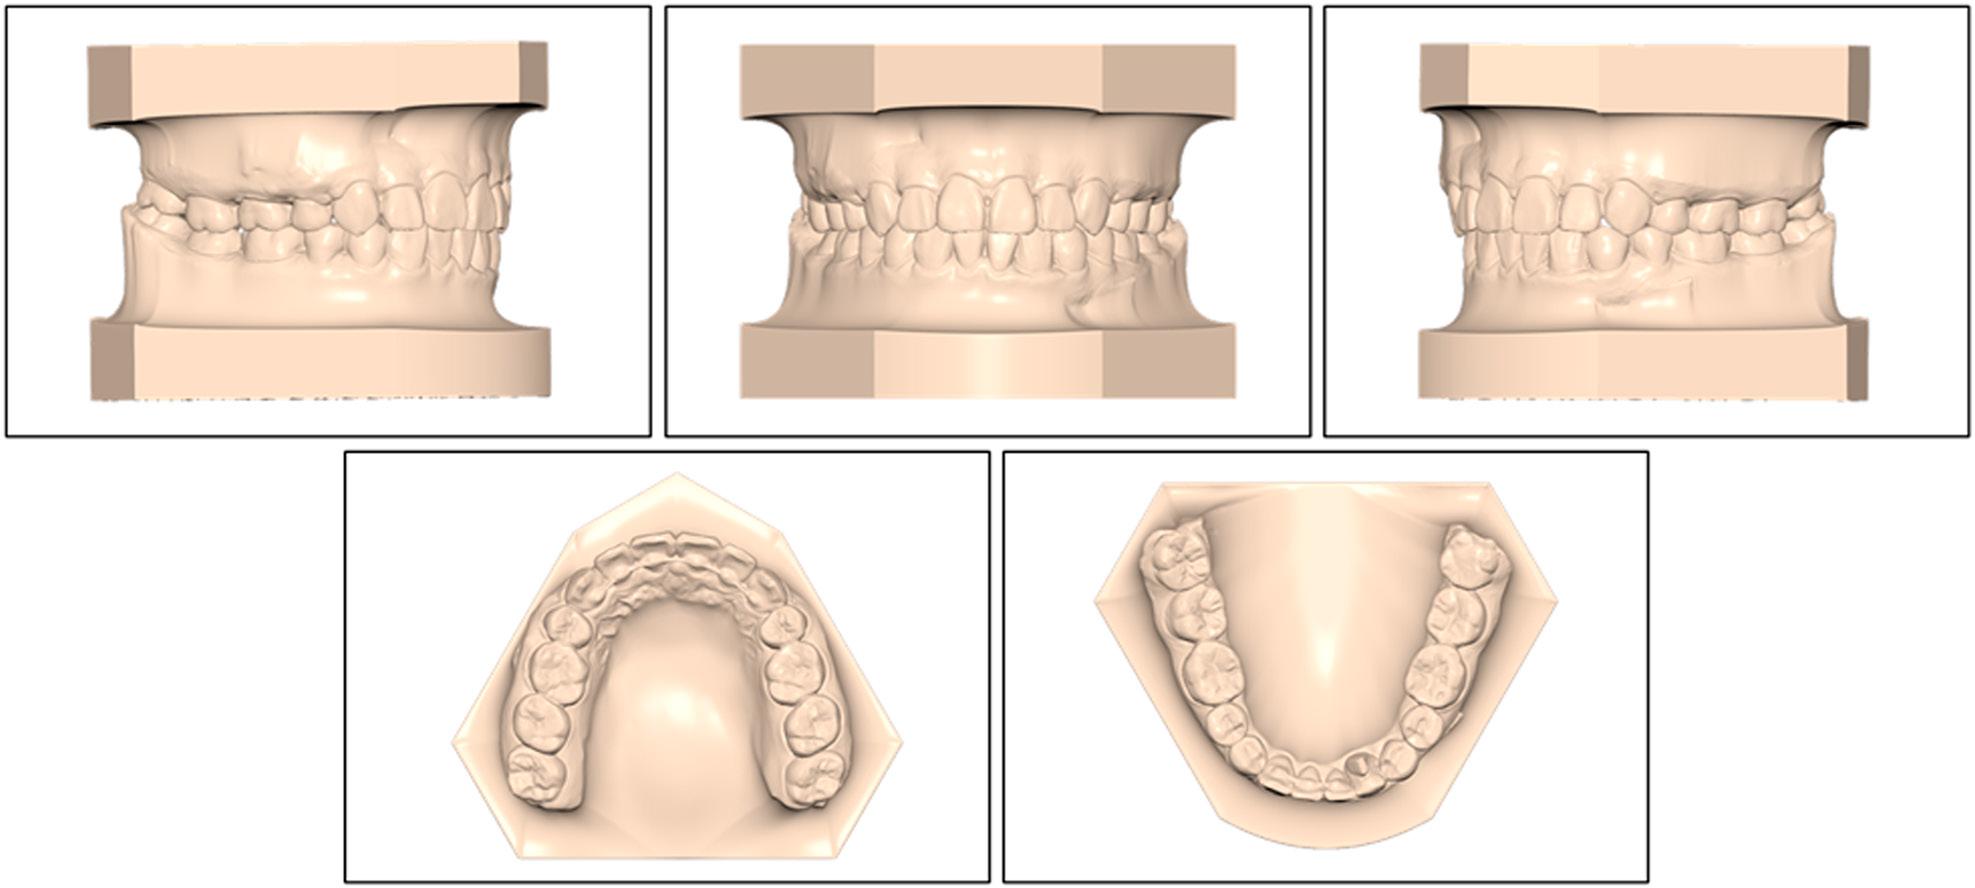

Figure 3.